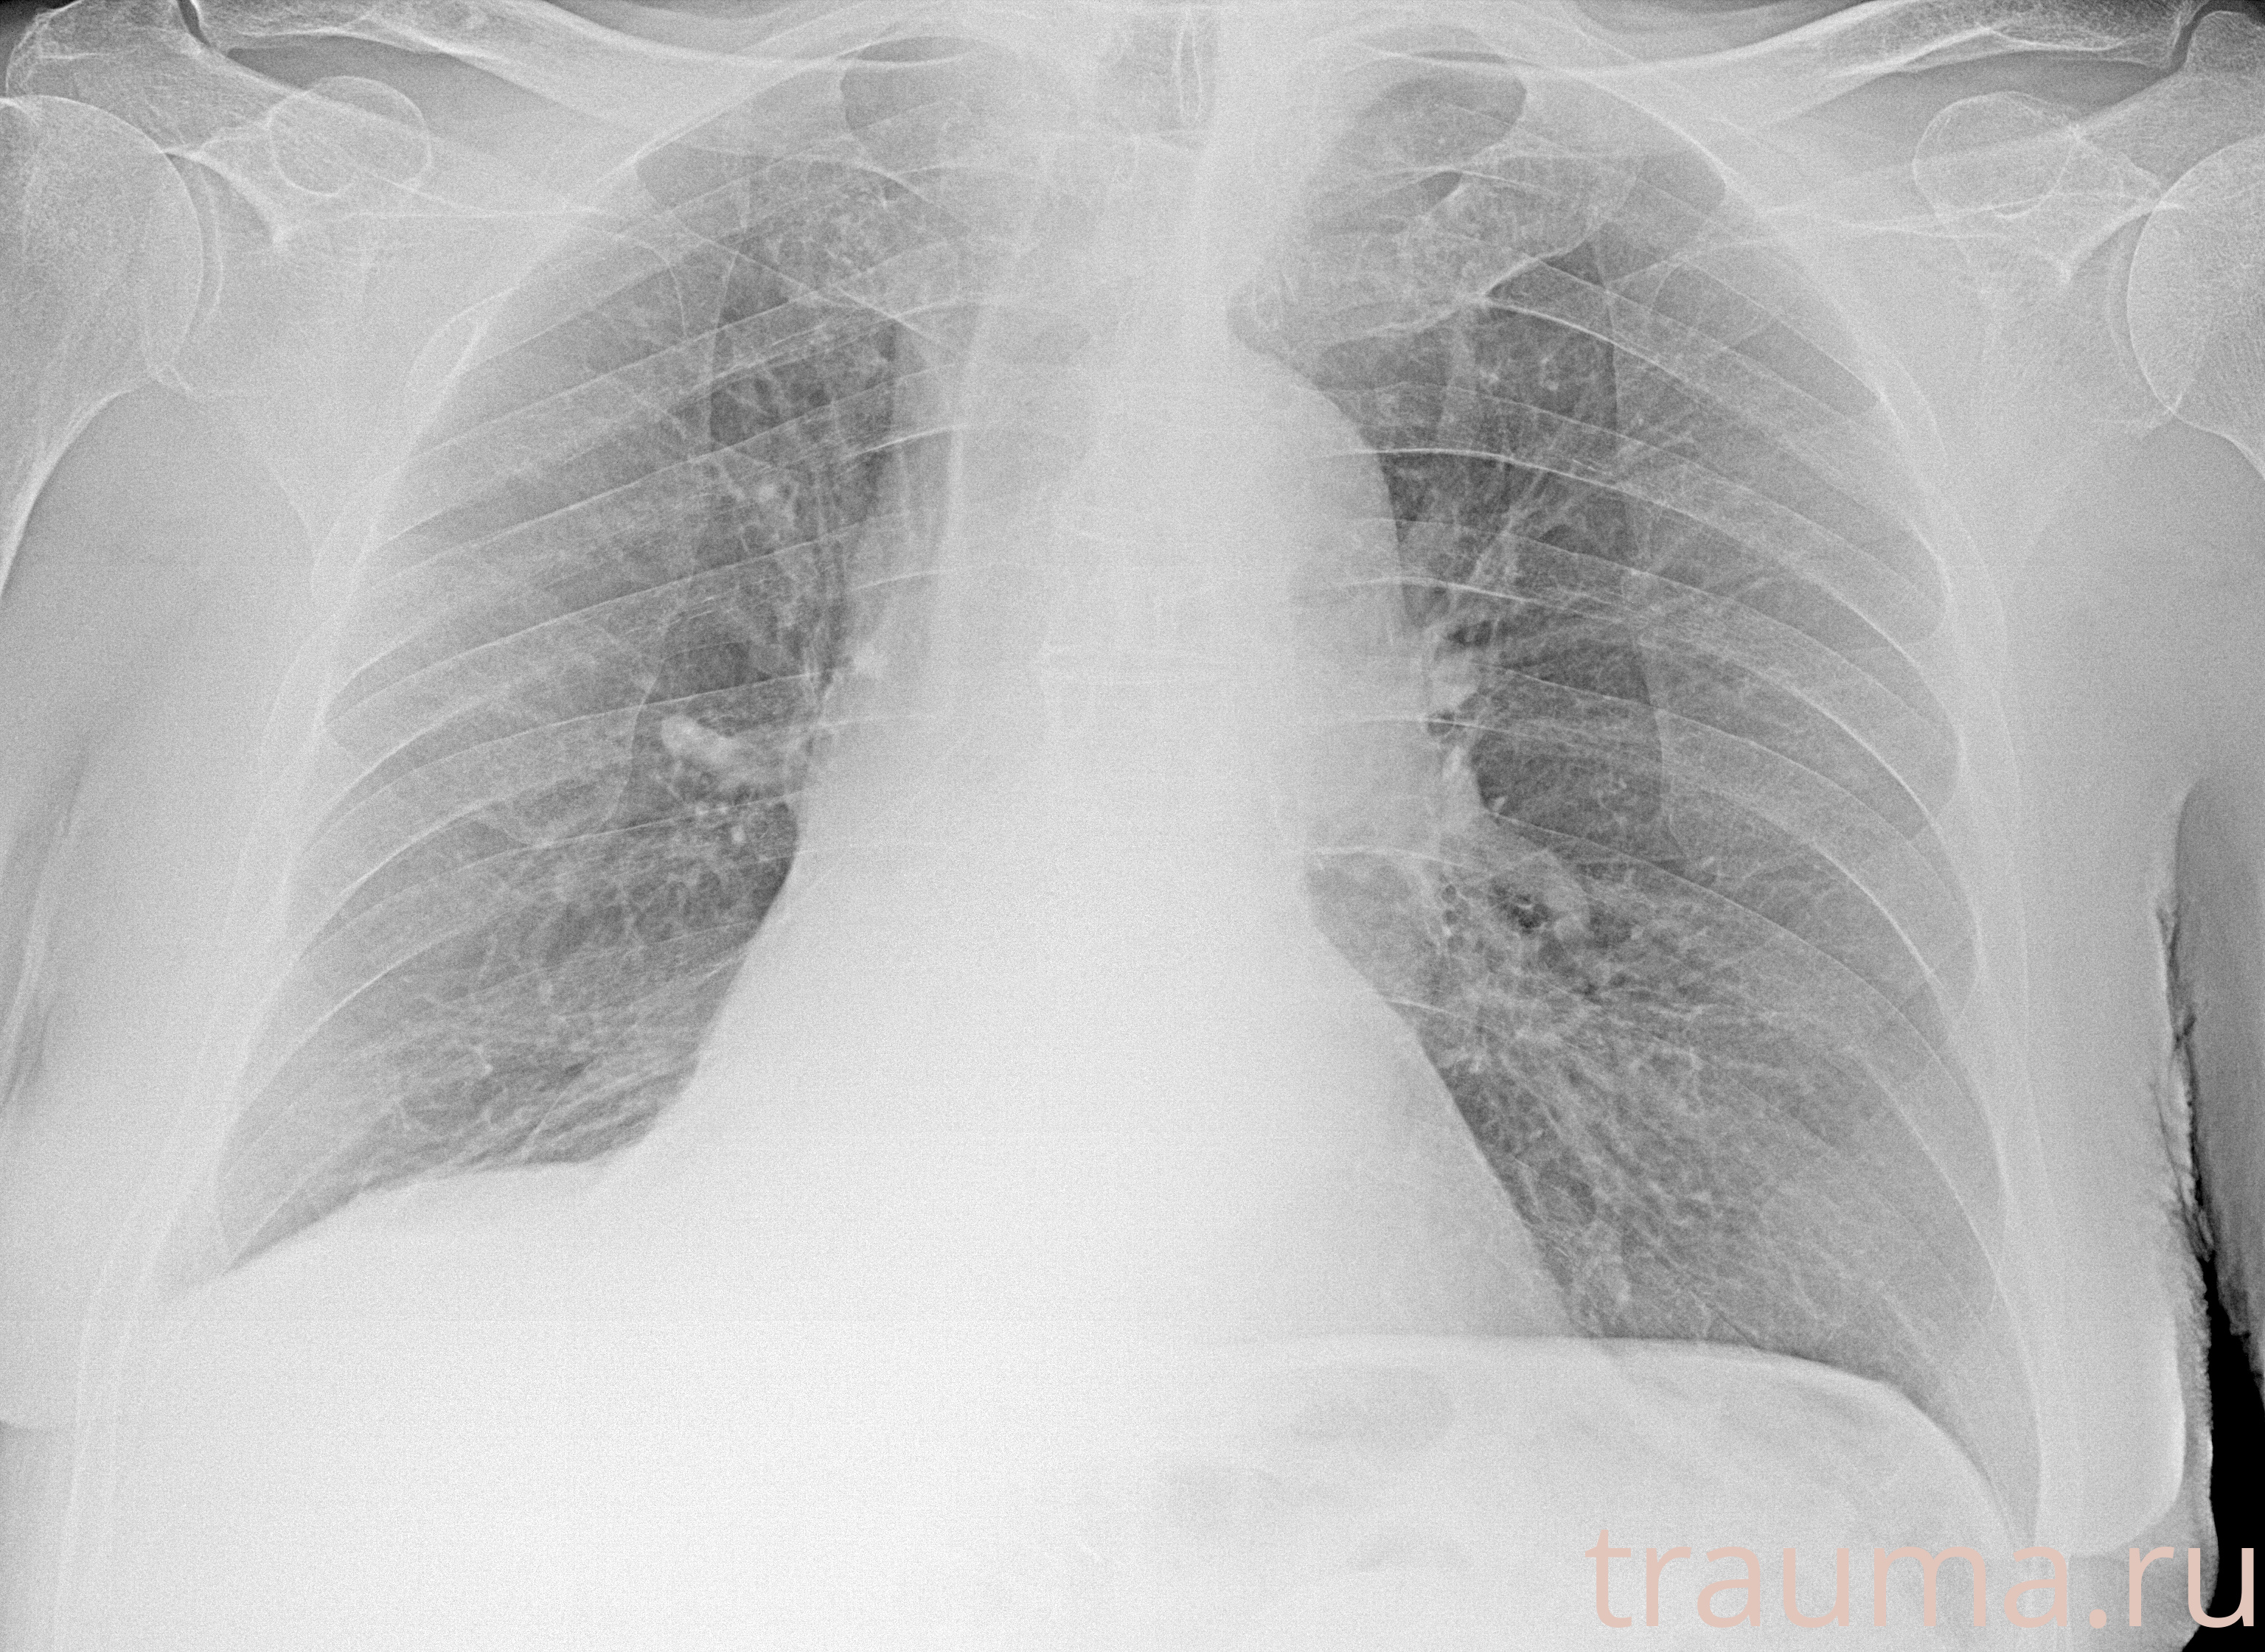

Рентгенограммы

Рентген на дому: по вашему адресу приезжает врач-рентгенолог, травматолог-ортопед с мобильным рентгеновским аппаратом, проводит диагностику травмы или заболевания, делает необходимые рентгенограммы, дает рекомендации по дальнейшему лечению. Получить качественные снимки в домашних условиях возможно благодаря уникальной методике, разработанной МосРентген Центром для института  Склифосовского